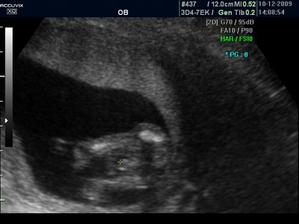

Zaplatila jsem si ale přesto UTZ a vypada to,že budeme mit chlapečka 🙂) pry tak na 80% jistota je vždy až po porodu 🙂)

CHLAPEČEK POTVRZENY Dr Břeštákem ))